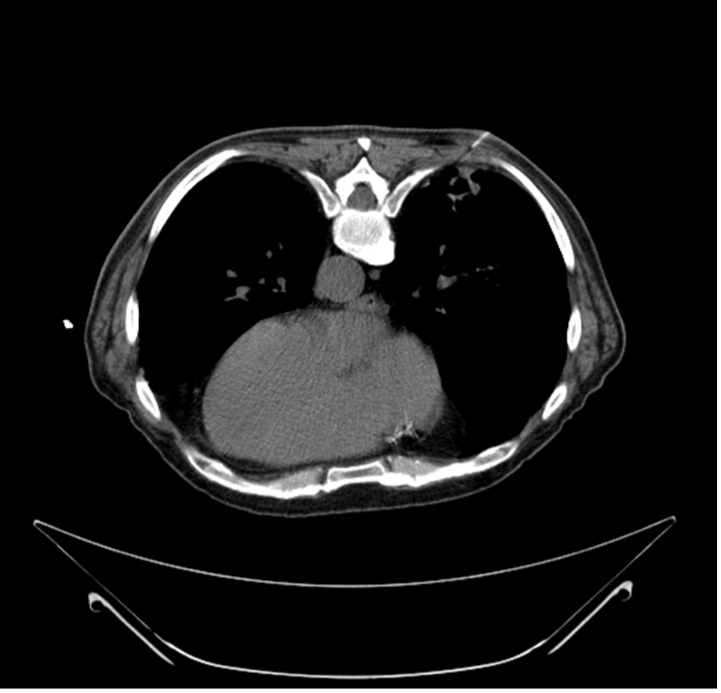

History. The patient had a medical history significant for invasive squamous cell carcinoma of the skin and presented with a new right lower lobe (RLL) lung mass. A prior bronchoscopy for the lung mass was inconclusive and led to a referral for a computed tomography (CT)-guided percutaneous transthoracic biopsy by interventional radiology (Figure 1).

Figure 1. The biopsy needle penetrating the right lower lobe lung mass during CT-guided lung biopsy. The patient was in the prone position.